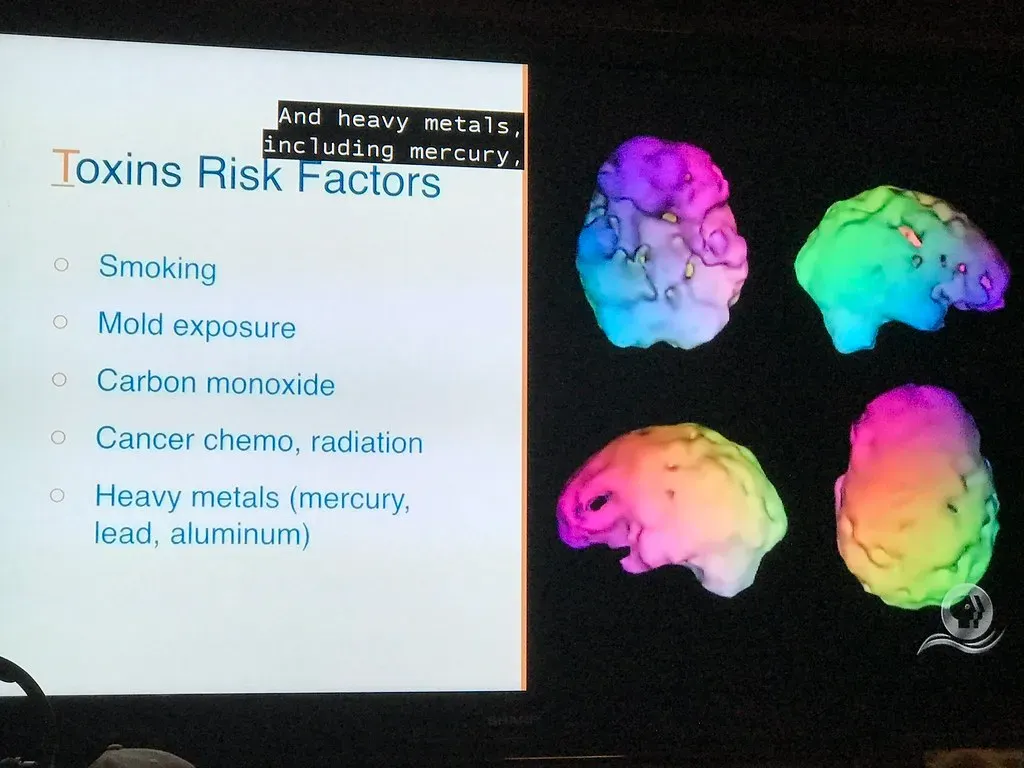

The Brain Under Threat: Microplastics, Metals, and Hidden Dangers

Here’s something genuinely alarming. Researchers from the University of New Mexico sought to see where microplastics accumulated in people. By analyzing organs from deceased individuals, the team found that microplastics and nanoplastics accumulated at especially high levels in brain tissue. Even more striking, liver and brain samples collected in 2024 contained significantly more plastic than those from 2016, hinting that environmental plastic exposure is rising fast. The brain, for all its brilliance, cannot filter out everything the modern world throws at it.

Meanwhile, other researchers are discovering unexpected links between everyday minerals and brain health. Imbalances in metals such as iron, copper, and zinc have long been linked to brain pathology, but when researchers at Harvard Medical School analyzed metals in human brain tissue and blood, lithium caught their attention. They found that lithium deficiency was associated with early physiological changes. Mice fed a lithium diet had reduced expression of genes related to neurodegeneration and increased expression of genes related to learning and memory. It’s hard to say for sure where this research leads, but the idea that a trace mineral could hold clues to protecting the brain is the kind of unexpected discovery that makes neuroscience endlessly fascinating.